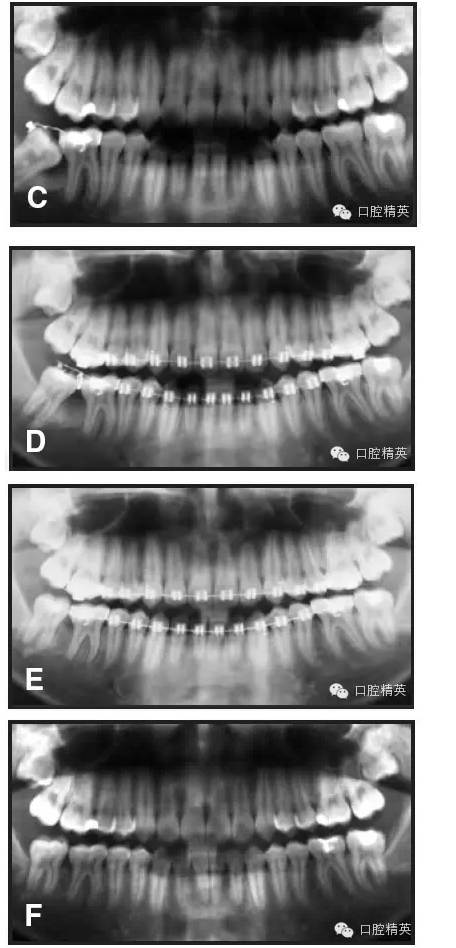

強(qiáng)烈推薦一種糾正傾斜磨牙的方法